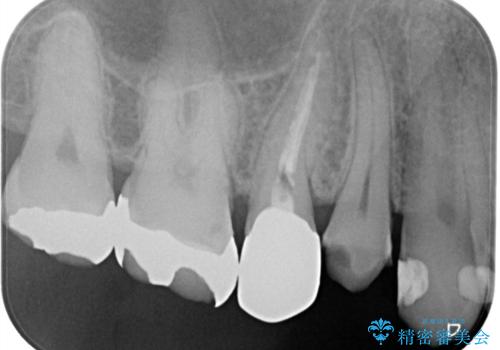

できるだけ歯質を残した1day治療 セラミックインレー

- 歯の詰め物が外れ、そのままにしていたのを治したいとのことで来院されました。残った歯質の量が少なく、できるだけ歯を残すために仮詰め期間の必要が無い1dayのセラミック治療を行いました。術後も経過良好です。処置においては虫歯も綺麗に除去しています。

1day治療は、仮詰めが不必要です。そのため、仮詰め期間中の残存歯質が欠けてしまうこともありません。また、口腔内の温度変化は食事等により50度近くあるといわれていますが、この間に仮詰めの材料は収縮・膨張を繰り返します。そこで生まれた隙間に汚れが入りこみ、これが接着力の低下やセット後の歯髄不快症状の原因となる可能性があります。1day治療にすることで、こうした因子を回避し歯の寿命を長くすることができます。